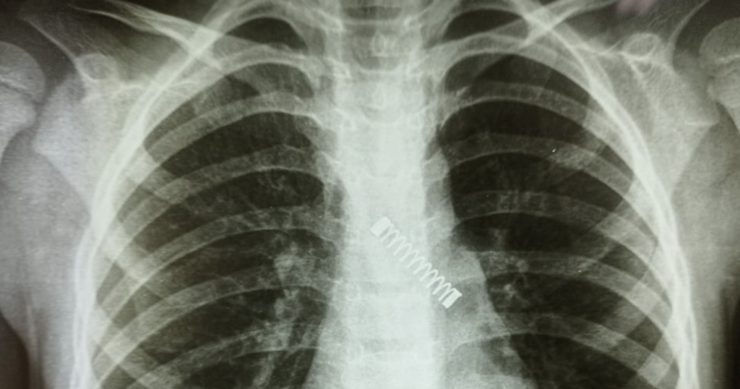

Rentgenske snimke su, naime, otkrile da dječak ima metalnu oprugu u plućima! Prebačen je u Nacionalni institut za respiratorne bolesti na hitno liječenje. Ondje je operisan i uspješno mu je uklonjena metalna opruga.

Dr. Carlos Morinigo izjavio je kako je operativni postupak bio komplikovan zbog vremena tokom kojeg je strano tijelo ostalo zaglavljeno u dječakovim plućima, kao i štete koju je prouzročilo u tom razdoblju.

Uprkos tome što je prouzrokovalo, kako su doktori utvrdili, “vjerovatno smanjenje kapaciteta pluća”, dr. Morinigo je izrazio očekivanje da će se stanje vjerovatno poboljšati kako dječak bude rastao. Doktor je objavio fotografiju pluća uz poruku: “Tri mjeseca kašlja. Nikad ranije nije bio odveden liječniku. Jadno malo stvorenje”, prenosi Slobodna Dalmacija.